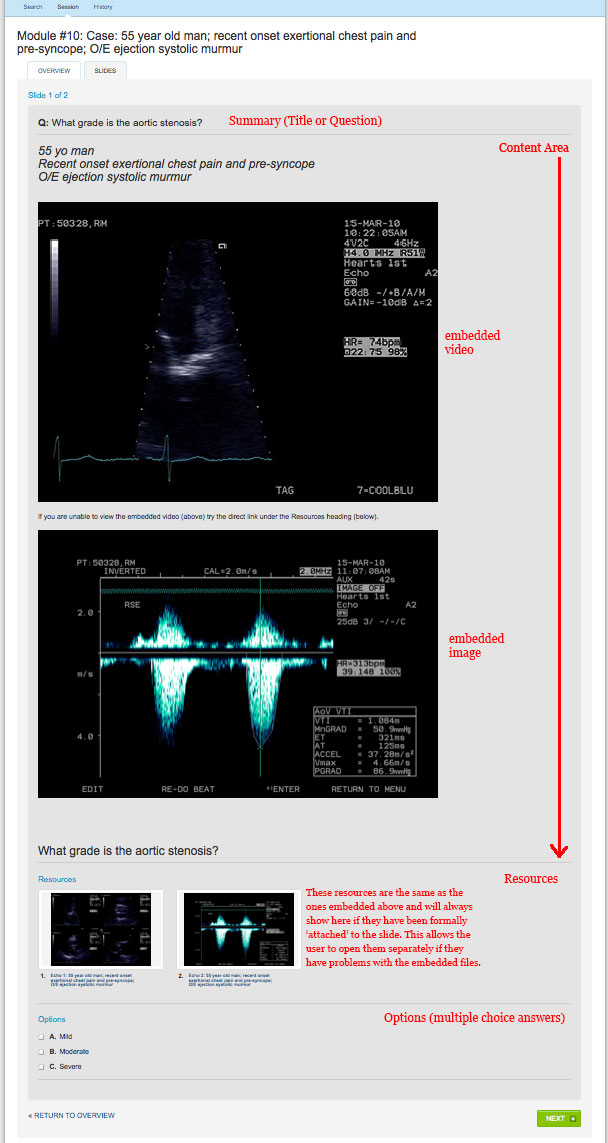

MappCPD_Module_Slide

Contributing Online CPD Modules